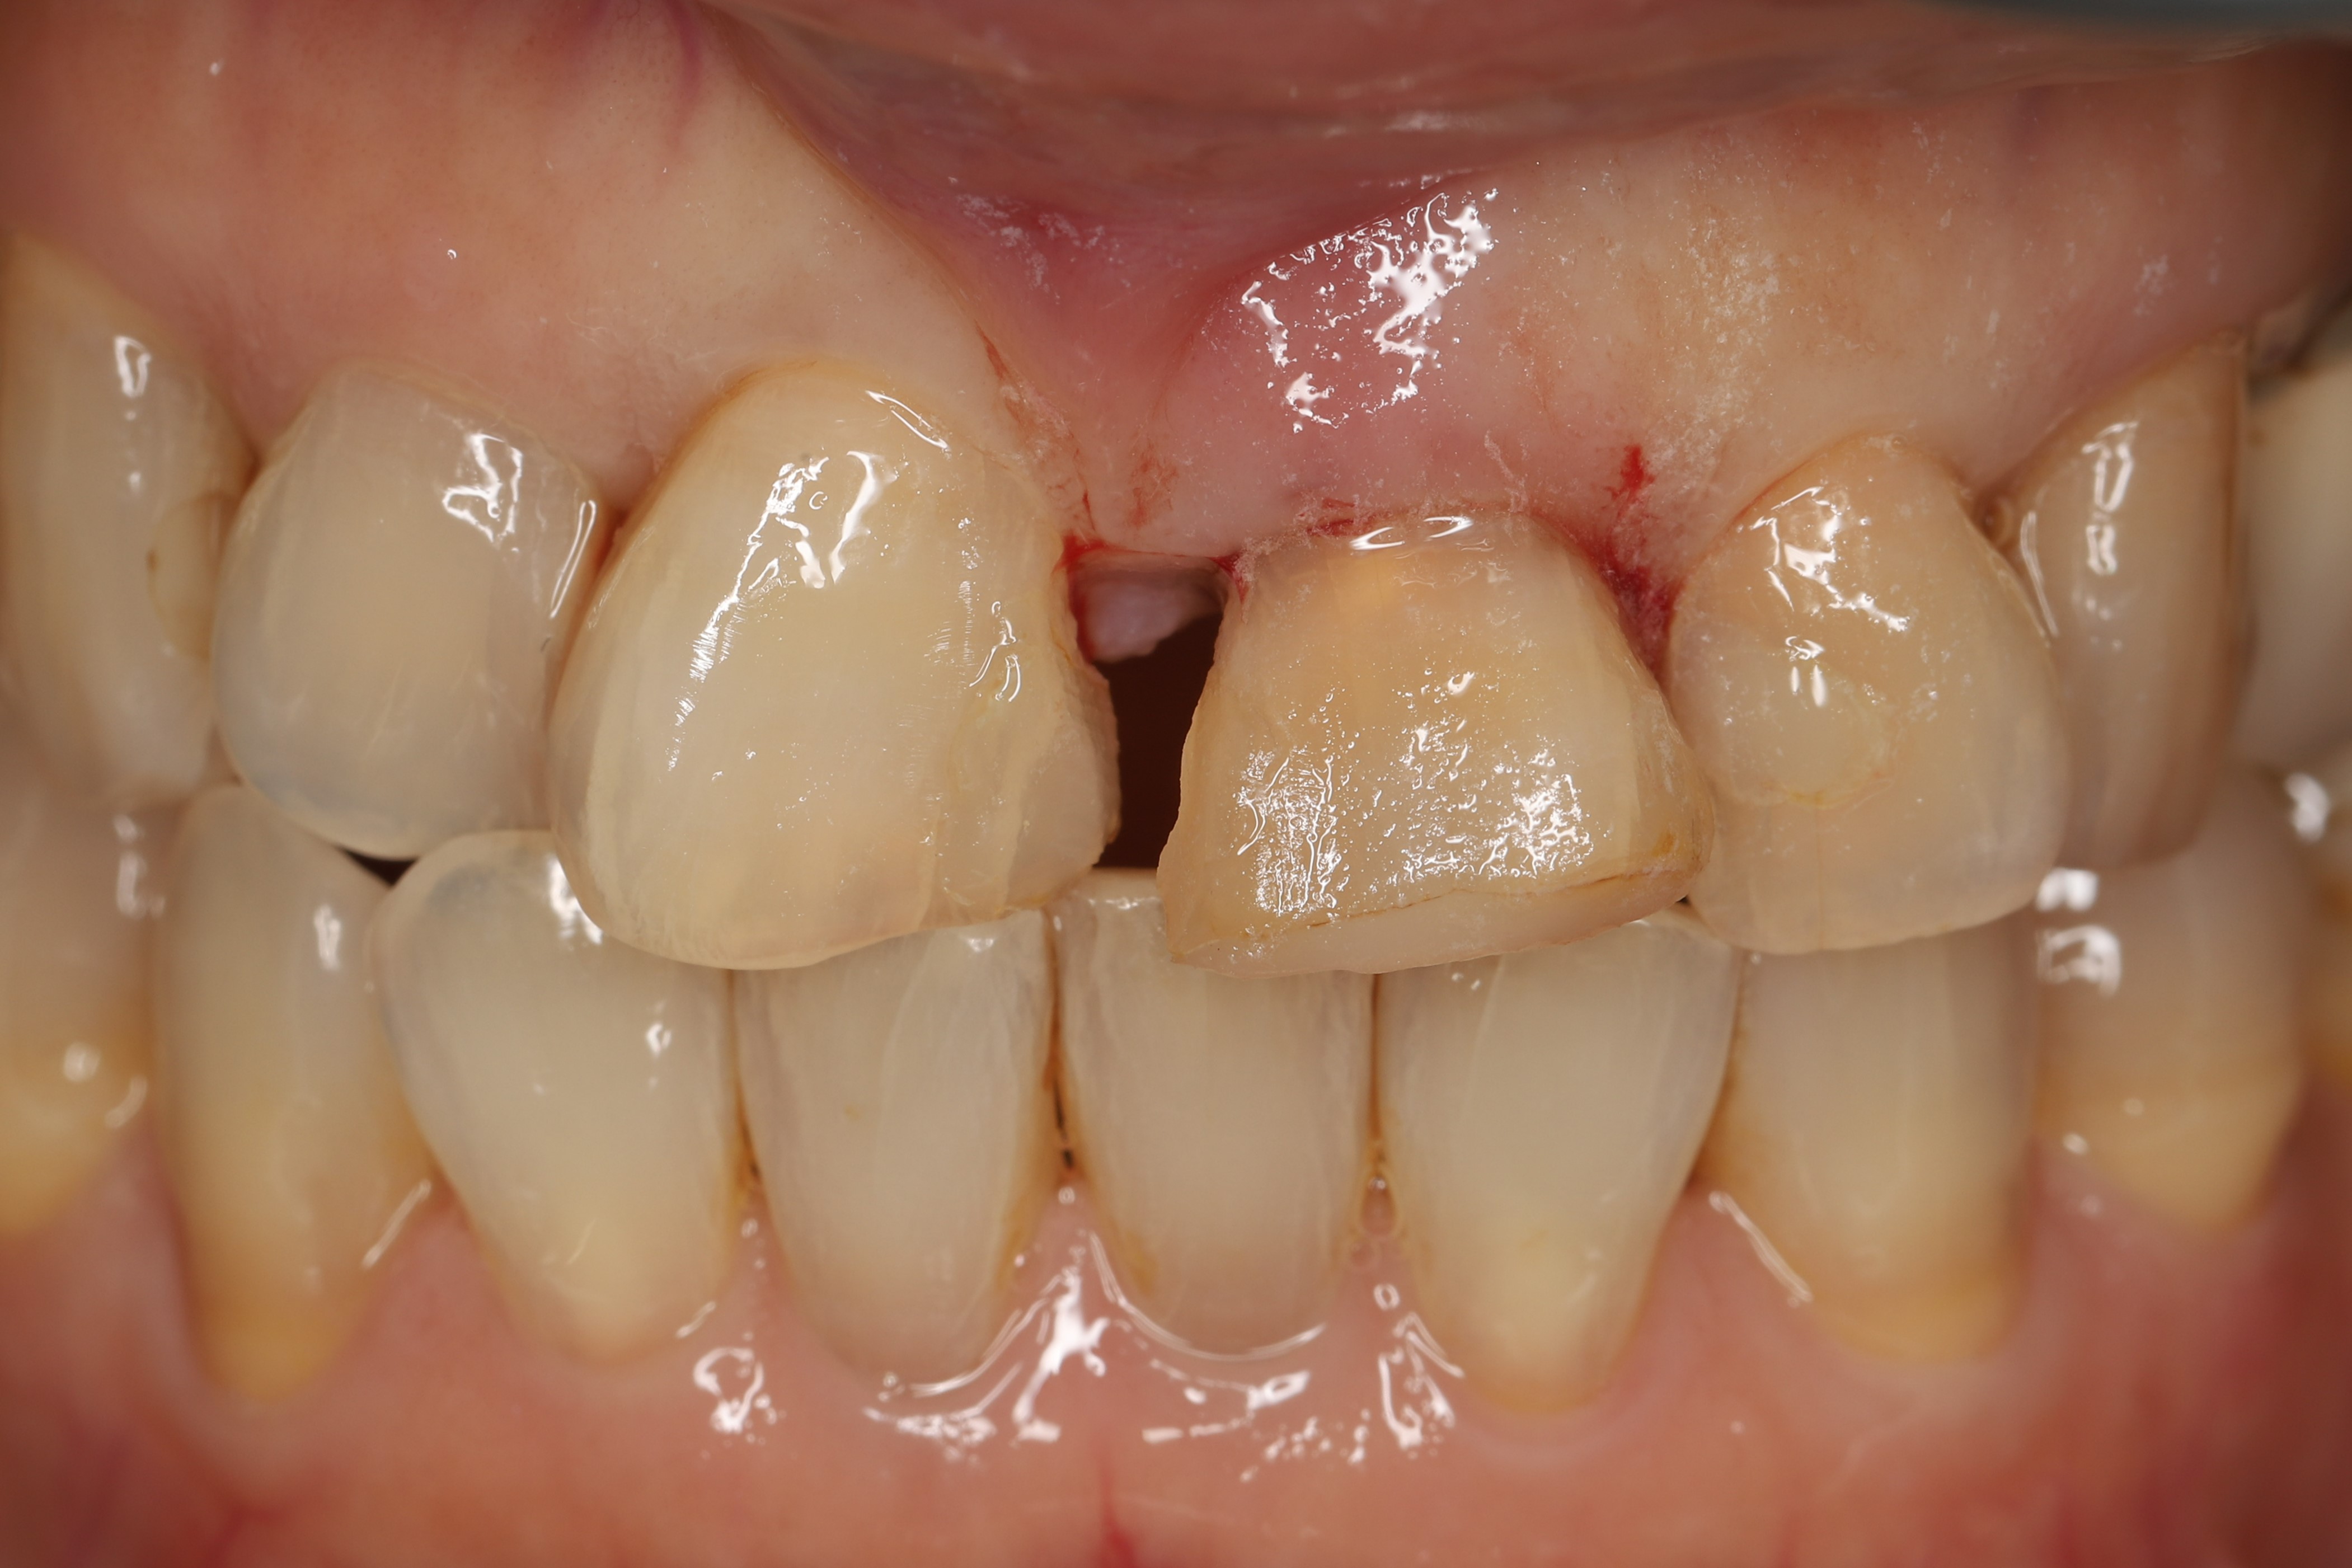

歯を抜いて歯茎が落ち着くまでの3ヶ月は仮歯で過ごします。画像は仮歯を外し、歯をセットする前の状態です。